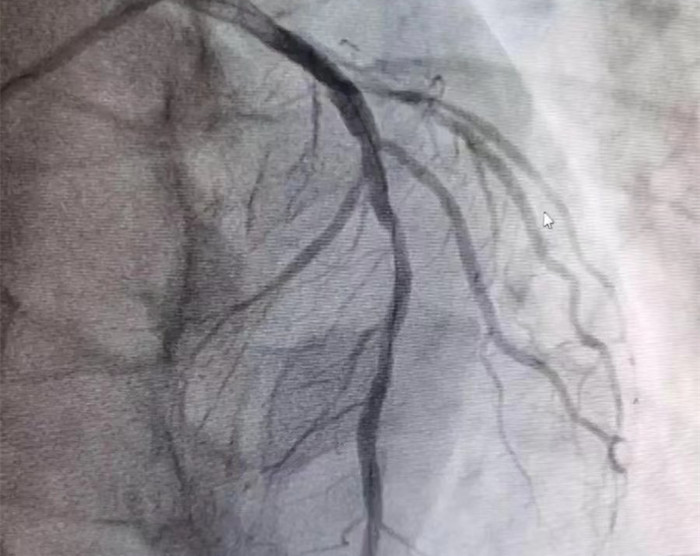

此时患者血压心律正常,双侧瞳孔等大等圆约0.4cm,光返灵敏,但意识仍不清。心内科主任张恒超与家属谈话,告知病情危重,考虑是急性心肌梗死,但还需要排除下蛛网膜下腔出血。家属全程配合医护人员迅速完成检查,排除了颅内出血的可能,签字同意后患者迅速被护送入DSA室。DSA团队顺利完成呼吸机辅助呼吸下急性心肌梗死支架植入术,术后患者顺利脱机,转病房观察。目前患者病情稳定。